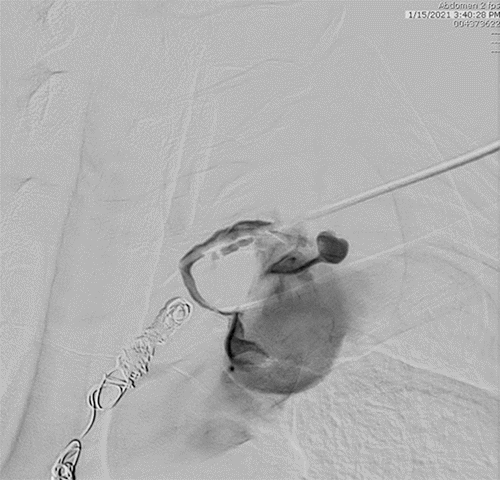

Figure 6. Initial Coil Placement at Defect. Published with Permission

Repeat chest CTA revealed a localized air-fluid collection in the left hemithorax, concerning for empyema. However, imaging review suggested an anatomic variant: a posteromedially positioned thoracic duct coursing along the left aorta, lateral to the vertebral column. Given this anomaly, a second IR embolization attempt was undertaken. Accessing the thoracic duct via the left neck proved challenging due to its proximity to the subclavian junction. Therefore, we opted for a re-approach of the previously embolized cisterna chyli through the epigastrium, followed by successful repeat embolization with glue (Figures 7-10).

Figure 7. Retrograde Access to Thoracic Duct at Subclavian Junction. Published with Permission

Figure 8. Retrograde Microcatheter Access to Thoracic Duct. Published with Permission

Figure 9. Repeat Access to Thoracic Duct. Published with Permission

The arrow indicates the placement of the catheter within the thoracic duct. Extravasation of contrast is noted at the puncture site in the cisterna chyli

Figure 10. Coil Pack Positioned Within Thoracic Duct. Published with Permission

Glue cast depicting the cisterna chyli